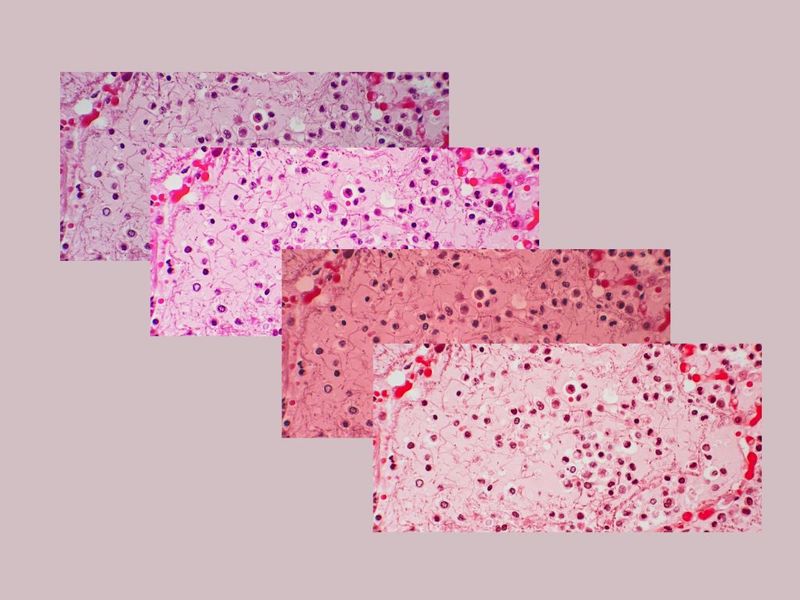

HMPV belongs to the ‘Paramyxoviridae’ family of viruses, similar to that of another respiratory virus, RSV. Both have a common seasonality. The symptoms are also similar. They are fever, cough, a runny nose, and wheezing – true for almost all respiratory infections.